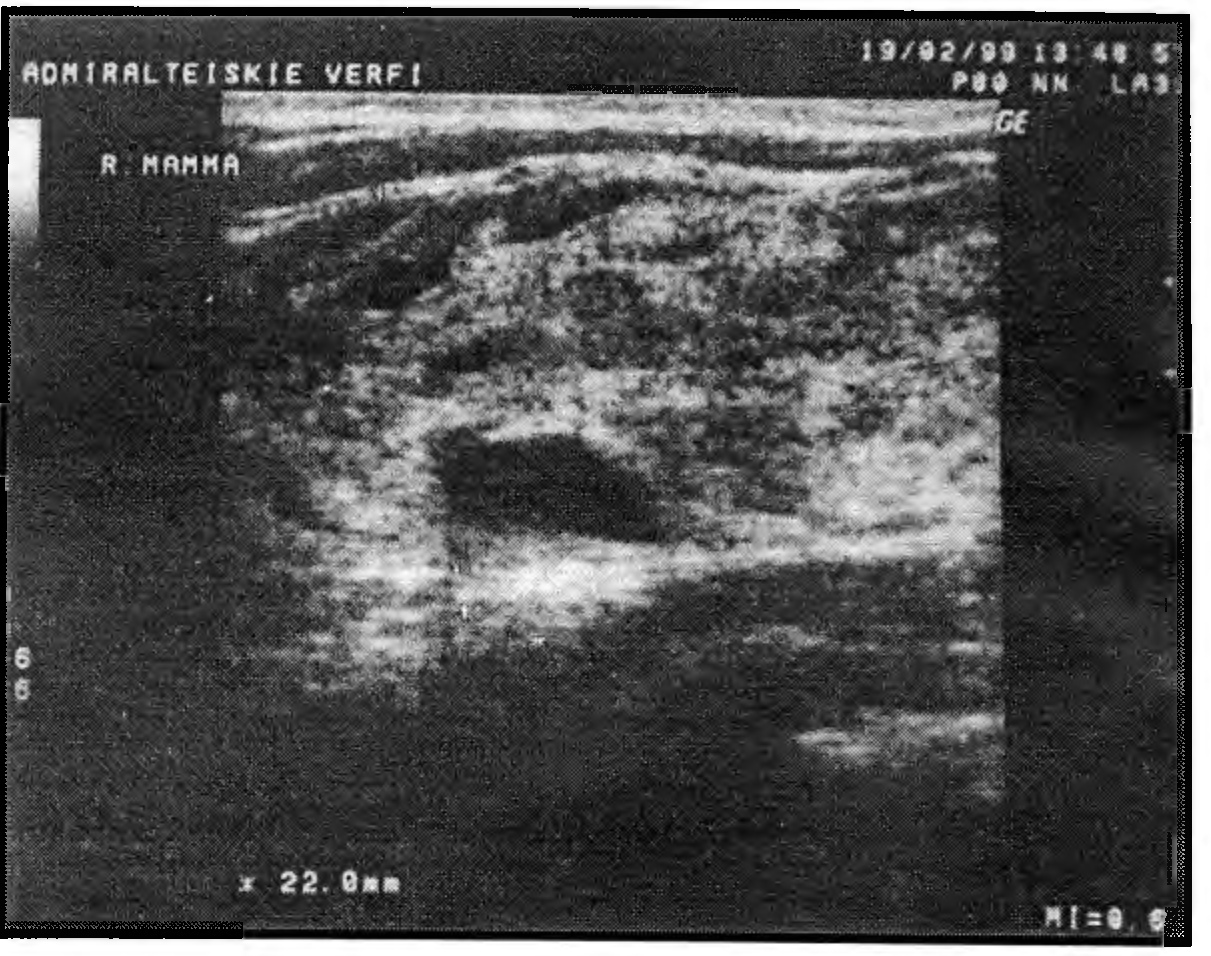

Смешанный вариант характеризуется сочетанием всех или большинства эхосимптомов диффузного фиброаденоматоза.

Рис. 9. Эхограмма смешанного варианта диффузного ФАМ у пациентки 40 лет. Утолщение слоя железистой ткани до 22мм. Киста. Показатели эхоплотности - повышенные (35-37). Дуктэктазия. Явлений возрастной инволюции нет.